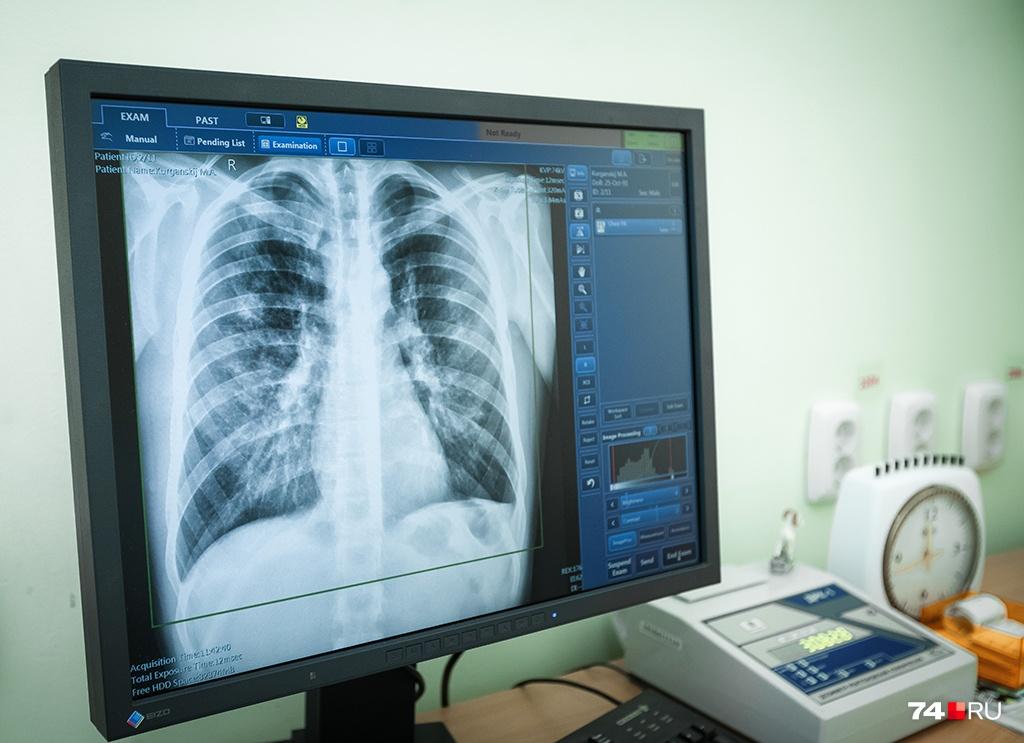

Продолжается серия кураторских визитов специалистов Иркутской областной клинической туберкулезной больницы в учреждения здравоохранения области. По поручению минздрава Иркутской области мы рассказываем коллегам, что нужно сделать для того, чтобы снизить бремя туберкулеза в регионе: как своевременно и качественно выявлять вновь заболевших; какие исследования проводить на местах; как грамотно вести реестры и др.